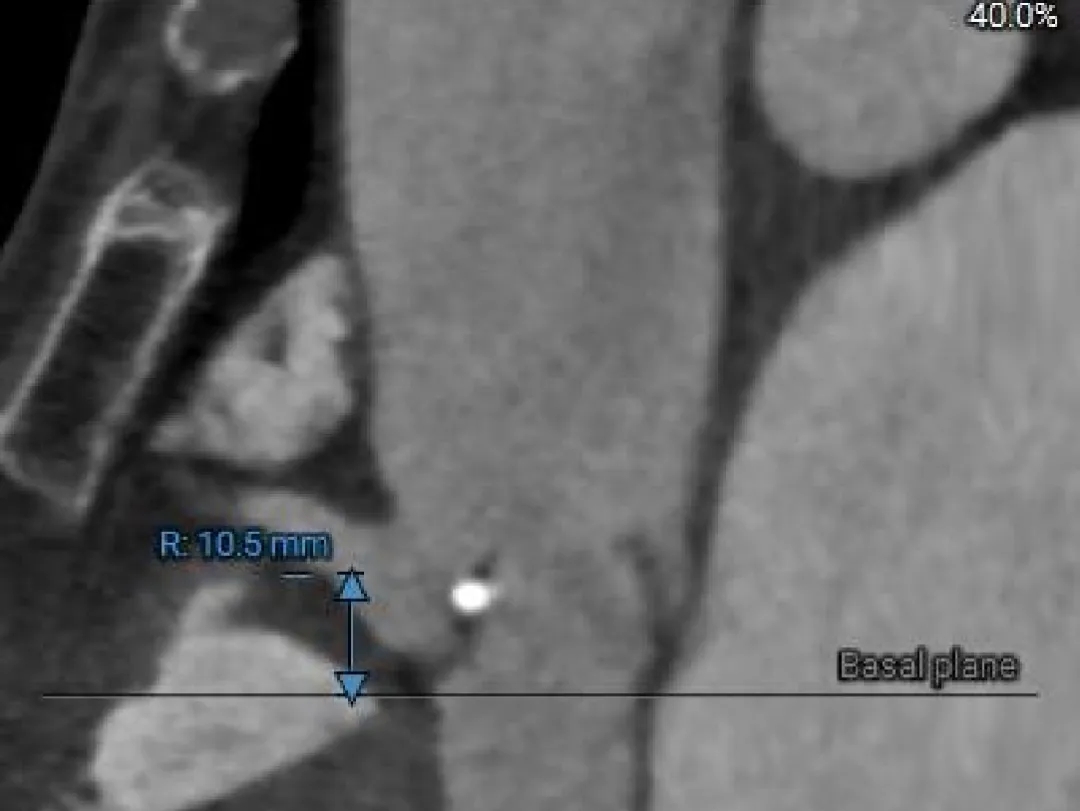

Right Coronary

10.5mm

RCA & Leaflet

13.3mm<13.5mm